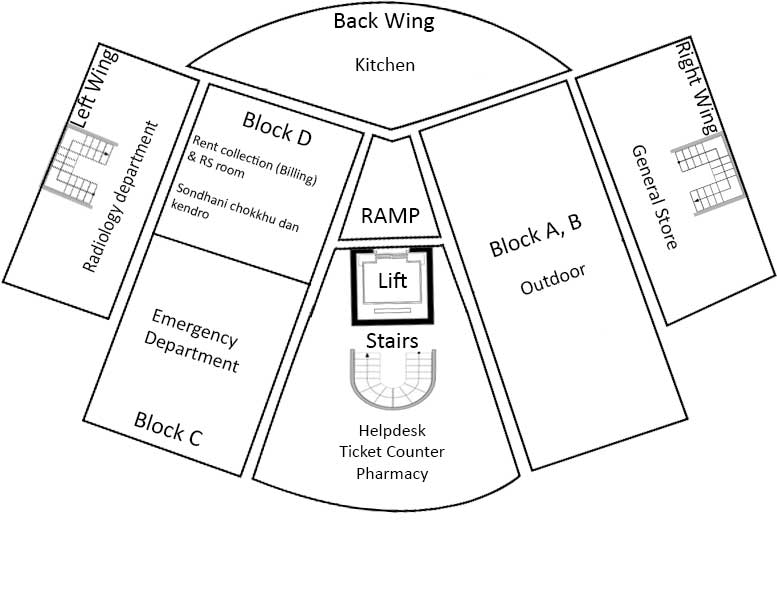

Outdoor

Kitchen

Emergency Department

Helpdesk and ticket counter, pharmacy

Radiology department

General Store